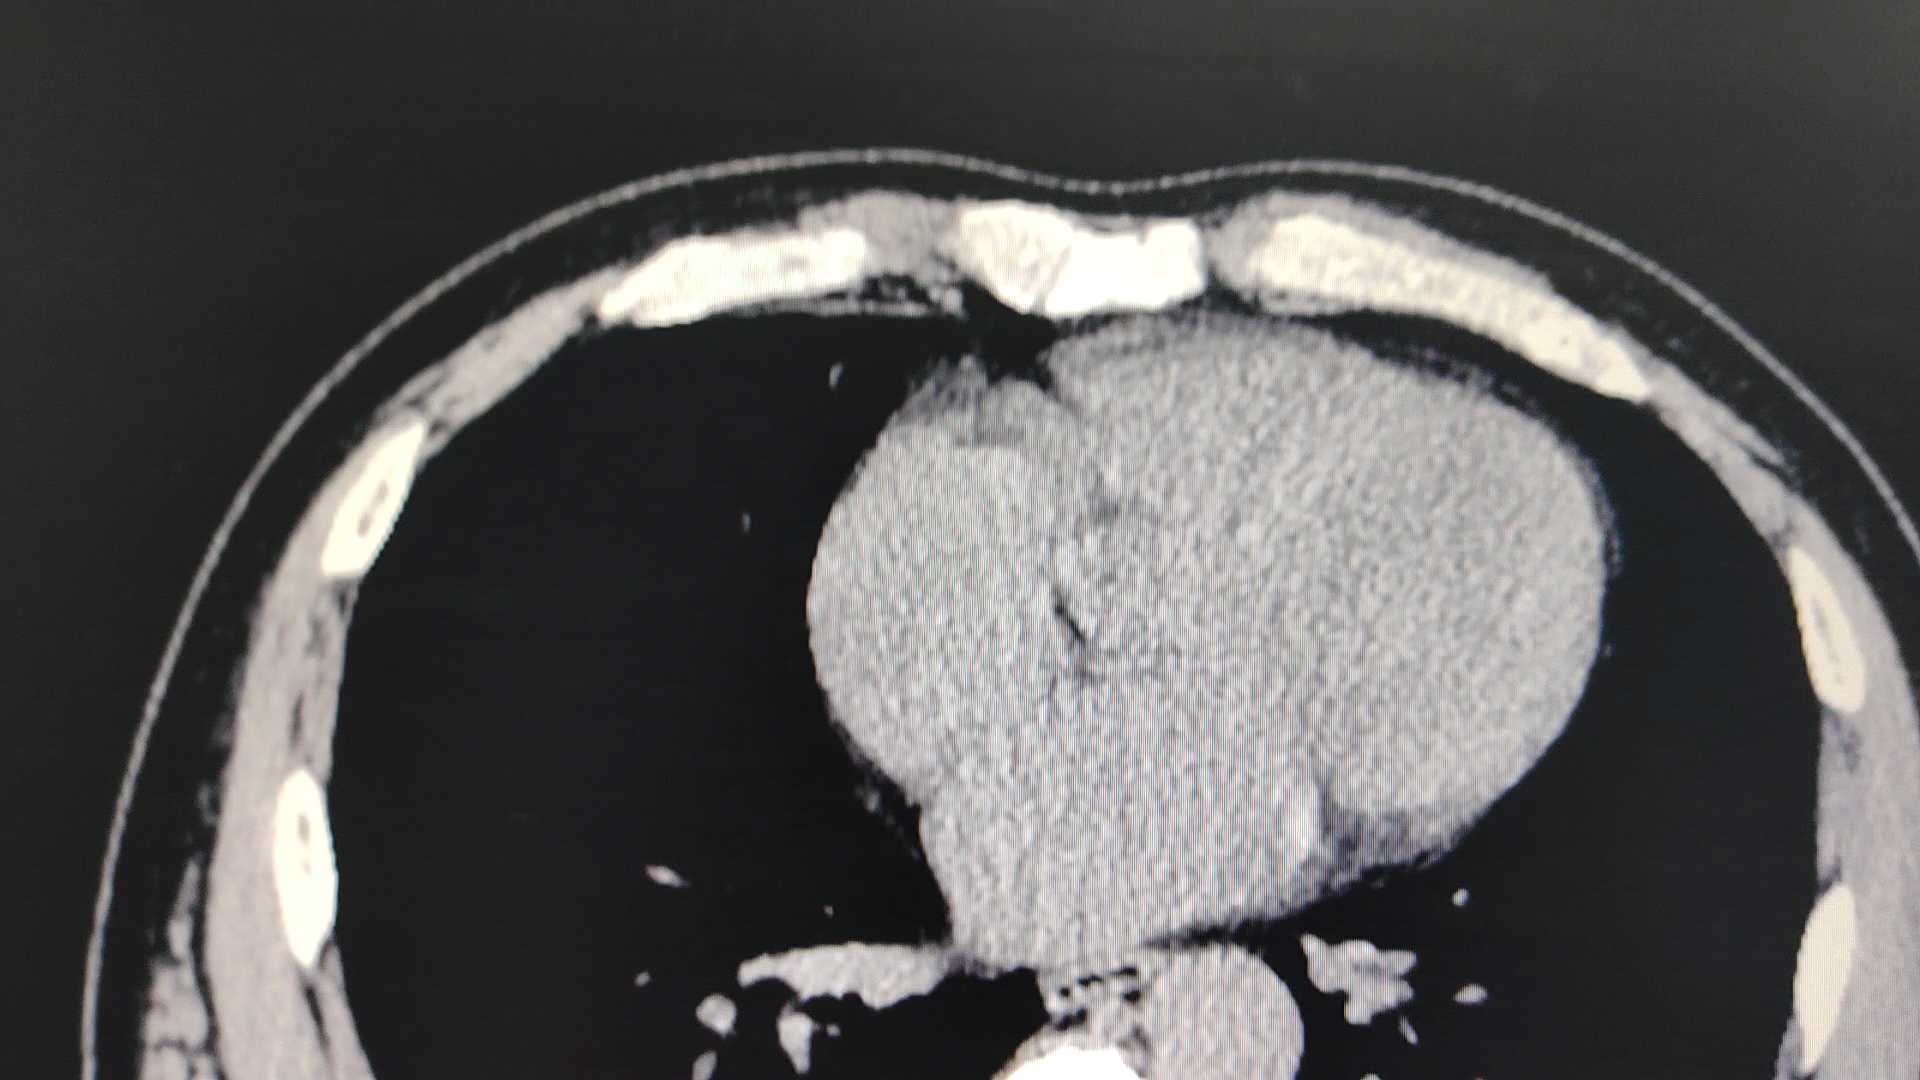

各位老师,看看这个腹腔左侧占位考虑什么病